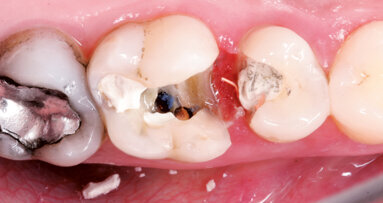

Kořenové perforace

Perforace v dřeňové dutině nebo kořenovém kanálku významně mění prognózu zubu. Oprava perforace pomocí biokompatibilního těsnicího materiálu jako je MTA může ohrožené zuby ušetřit (Mente a spol. 2014) (obr. 3a–e).